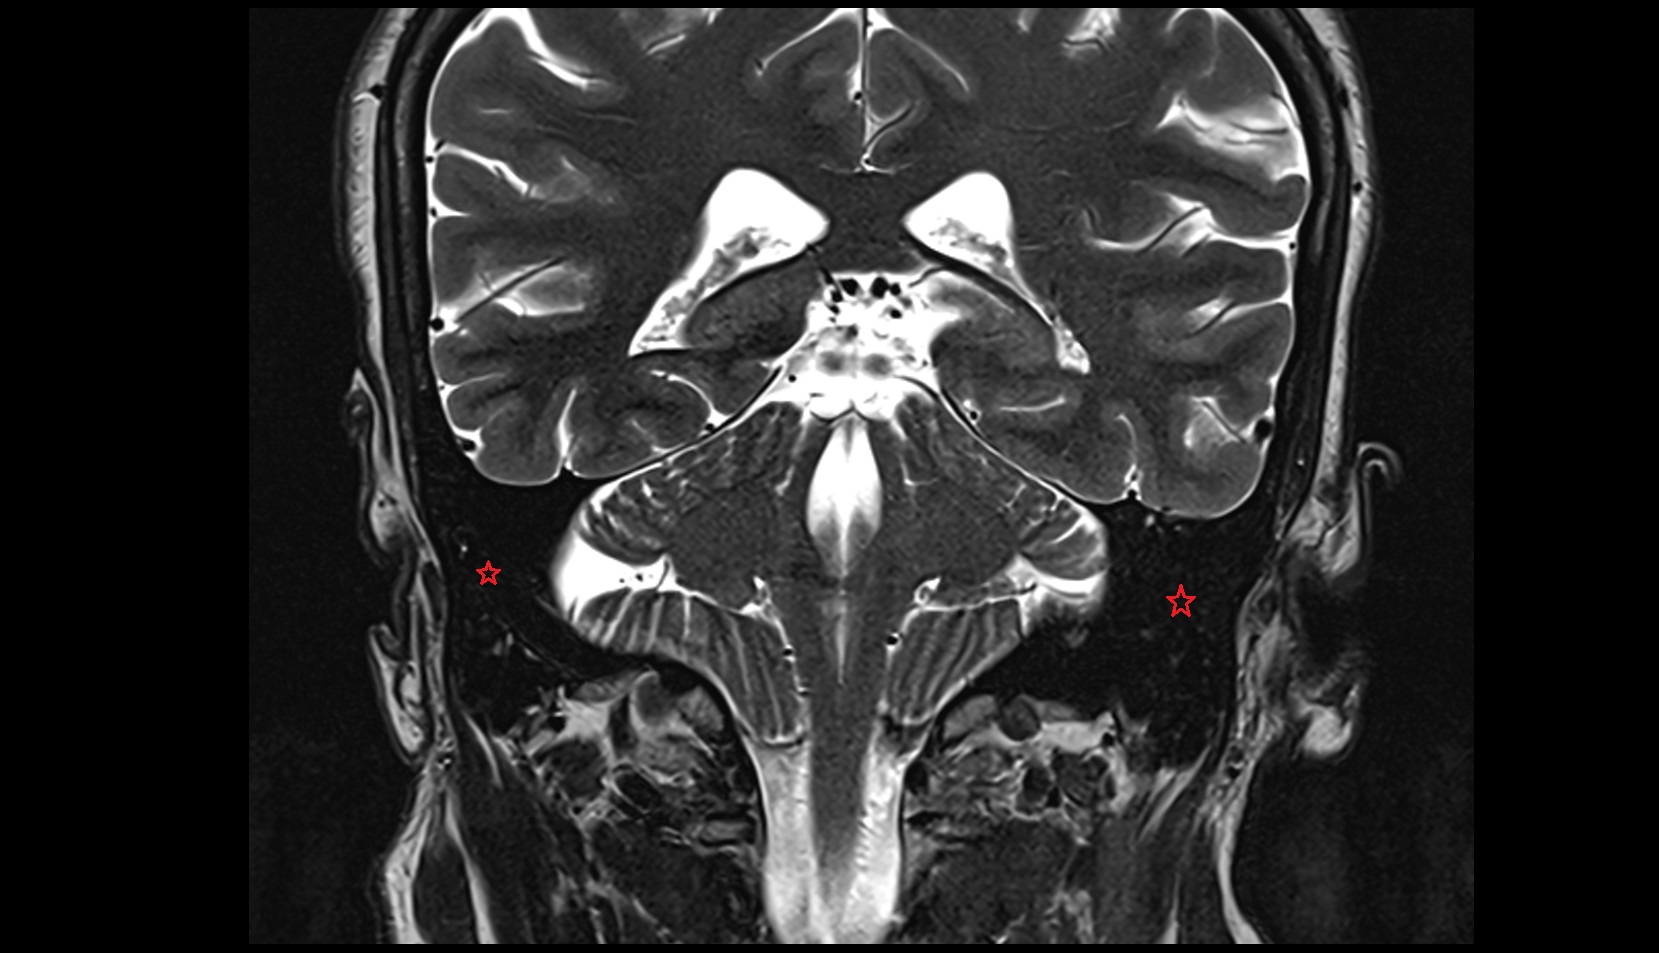

- Cerebellopontine angle

- Lateral cerebellomedullary cistern

- Pontocerebellar cistern

- Cerebellopontine cistern